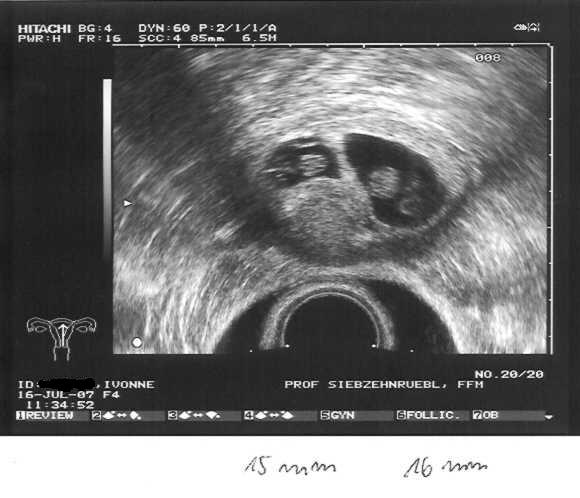

Ab heute ist es Amtlich wir bekommen Zwillinge

beide Herzlein schlagen. Wir können unser Glück garnicht fassen.

Den US hat heute Fr. Dr. Weidner gemacht, da in der Praxis wohl jemand Kollabiert ist und sie Daher unter Zeitdruck gestanden haben. Beide Babys waren gut zu sehen das eine ist 15mm und das andere 16mm groß. Allerdings hat Fr.Dr Weidner gesagt das ich von der Entwicklung her erst in der 7+6 wäre.

US 16.07.07 2 Herzlein schlagen Zwillinge

Schon schön anzusehen dein US Bild, SCCCHHHÖÖNNNN.